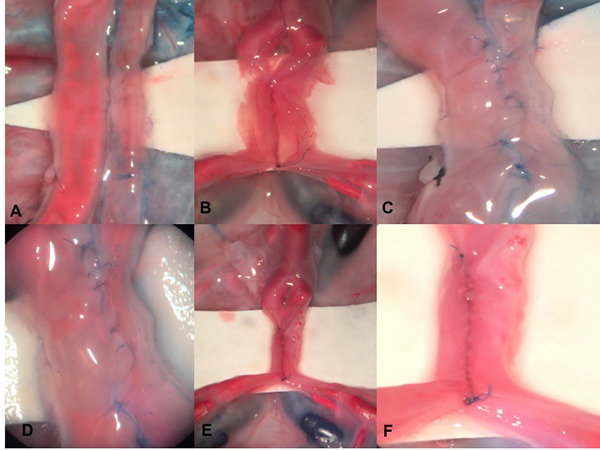

Latero-Lateral

Figura 5: Anastomosis laterolateral. A. Placenta previamente preparada con tinción vascular, se fijan sedas temporales a una distancia de 1.5-2 cm cada una, se realiza arteriotomía longitudinal en ambas arterias. B. La anastomosis se inicia en el extremo inferior y en la pared posterior de las arterias con sutura continua simple 9-0. C. Se continua con el extremo superior y la pared anterior de los vasos. D. Se retiran las sedas, se verifica permeabilidad de la anastomosis, no se evidencian fugas en la misma. E y F. Anastomosis laterolateral en un vaso tratado con técnica de coloración vascular con silicona.